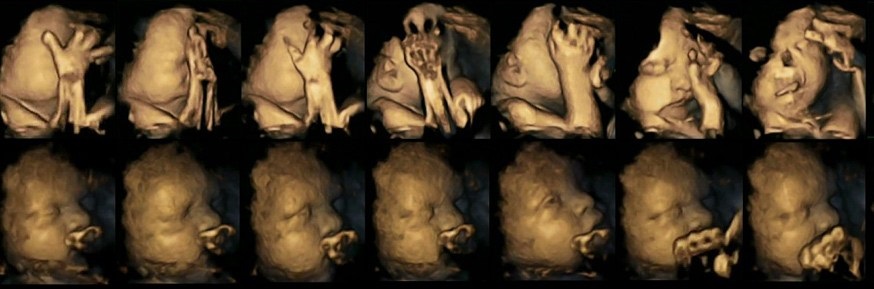

4D ultrason görüntüleri.

20 anne üzerinde 4D ultrason taramaları üzerinde çalışan Dr. Nadja Reissland, sigara kullanan anne adaylarının dördünde fetusun gelişiminin 24. 28. 32. ve 36. haftalarında binlerce minik hareket tespit etti. Bu hareketler, daha çok fetusların yüzlerine dokunması olarak gözlemlendi. Dr. Reissland’ın elde ettiği sonuçlar arasında sigara kullanan annelerin, bebeklerinin merkezi sinir sistemi gelişimini yavaşlatabileceğini de ortaya çıkardı.